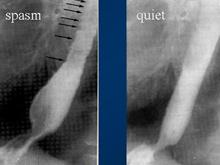

弥漫性食管痉挛是以高压型食管蠕动异常为动力学特征的原发性食管运动障碍疾病,病变主要在食管中下段,表现为高幅的、为时甚长的、非推进性的重复性收缩,致使食管呈串珠状或螺旋状狭窄,而上段食管及食管下括约肌常不受累。本病临床较为少见,常以慢性间歇性胸痛和吞咽困难为主要症状,任何年龄均可发病,多见于50岁以上,无明显性别差异,其病因及发病机制尚不十分清楚。本病多见于50岁以上的人,但任何年龄的成年人均可发病。无明显性别差异。